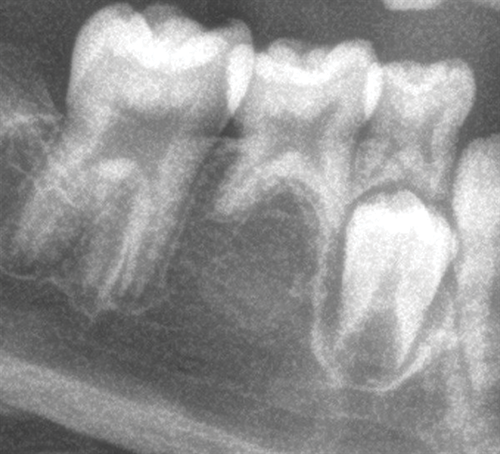

Another contributor suggested waiting until the 3s and 4s erupt, noting that doing so might also help stimulate the eruption of the 8s. Others agreed that timing would be key, and that allowing additional eruption before intervention could provide a clearer picture of space management and potential drift (Figs. 2-4). Still, some clinicians favored a more proactive approach, suggesting that early extraction of the E’s might encourage the 6s to drift mesially and simplify future treatment.

Fig. 2